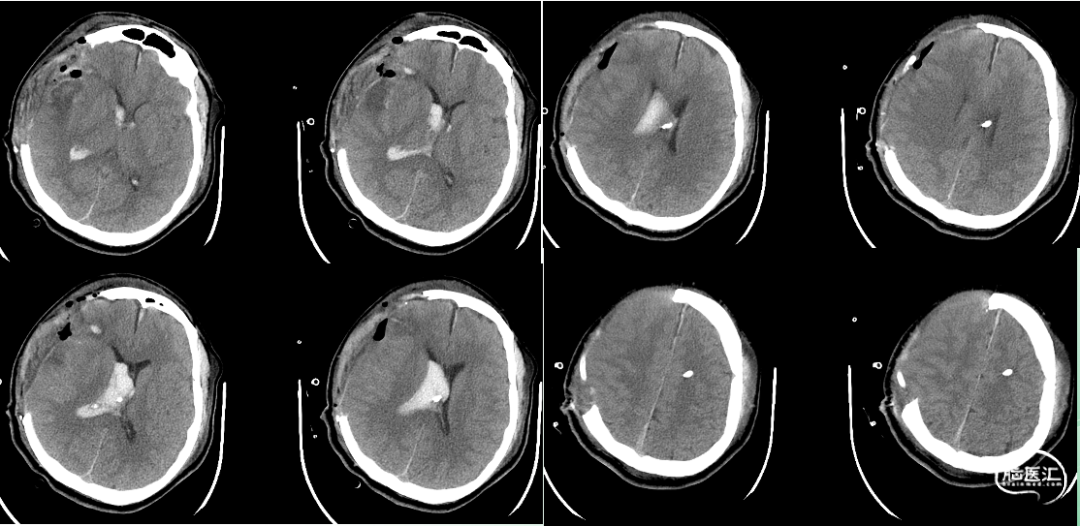

出院时影像

出院时情况

患者偶有烦躁、偏执、哭闹,可遵嘱动作,独立行走,无发热,无呕吐及四肢抽搐,大小便正常。

查体:神志清楚,左侧瞳孔直径2.5mm,对光反射灵敏,右眼眼球摘除术后,头部切口愈合良好,骨窗压力不高,双肺呼吸音粗,未闻及啰音,腹软,左侧肢体肌力4+级,右侧肢体肌力5级,肌张力正常,生理反射存在,病理反射未引出。